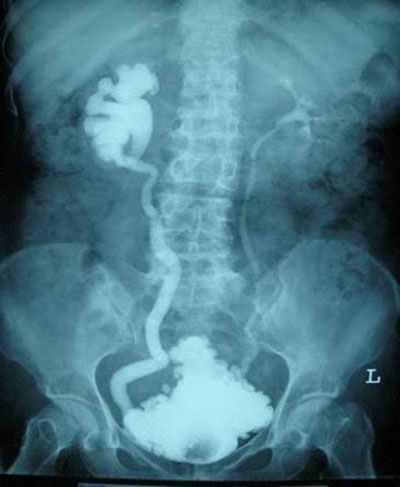

输尿管反流所致肾脏不可逆损伤

并发症互相影响